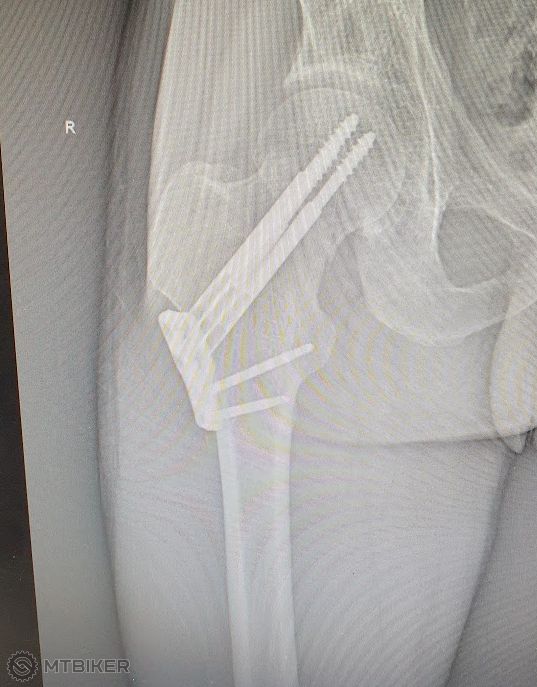

Mali ste už na biku nejaký drsný pád alebo úraz. Ja zatial len zlomený malíček ale to bolo už dávno.

Pripájam obrázok z minulého roka z Livigna, dúfam že sa Samko nenaštve.

Dosiel si po svojich ?

Ja som min rok odbajkoval asi 10 km este domov, citim som bolest bol som v tom, ze mam narazeny bok. V noci to bolo dost zle no a rano mi spravili RTG, v ten isty den mi to zosrobovali... Celkom na mna pozerali, neviem ci nemam posunuty prah bolesti.